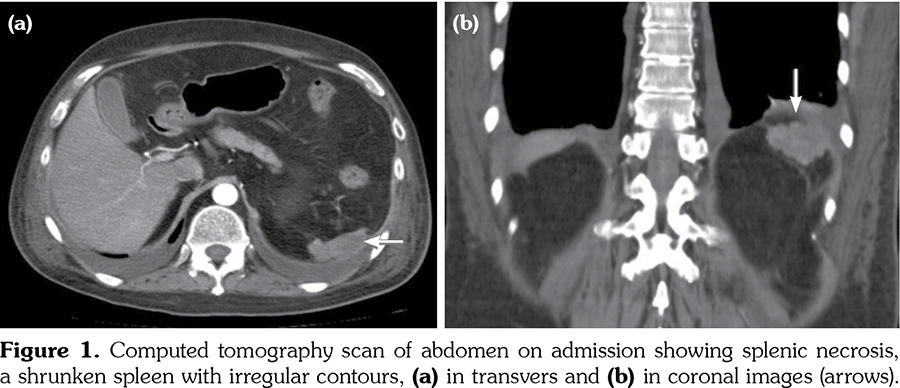

In clinical admission, his physical examination showed no evidence of systemic infection with a body temperature of 37.2°C. Laboratory findings at his first admission were summarized in Table 1. Computed tomography (CT) scan revealed a cavitary lesion of 6 mm in diameter located in the left upper lobe (which was also seen in his previous chest CT) besides a shrunken spleen as a recent finding (Figure 1).

To date, splenic involvement has been reported rarely in GPA; in fact, it is thought to be underestimated as it is often asymptomatic.[1,12] Spleen pathologies that can be seen in GPA include splenomegaly, capsular adhesion, splenic artery-vein thrombosis, granuloma formation, splenic infarct and hemorrhage, rupture or abscess as a complication of splenic infarct.[1,12] In GPA, splenic infarct occurs as a result of occlusion of the distal part of splenic artery and its branches.[13] In our patient, splenic findings seen in the CT scan possibly improved as a consequence of previous splenic infarctions. Although Doppler ultrasonography of the splenic artery and vein could not be performed, septic embolism was ruled out by echocardiography. Splenic infarct and rupture have also been reported during acute CMV infection.[14] However, in our case, a shrunken spleen, rather than a recent infarct, was detected during CMV colitis, which suggested that spleen involvement could be primarily related to GPA.

Although particularly left upper quadrant pain may accompany spleen infarction, splenic involvement was detected incidentally without any abdominal pain.